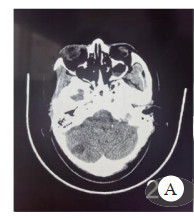

头胸部CT(图 3、图 4),分别提示右侧小脑半球、右侧枕叶片状低密度影,局灶性脑水肿以及双肺多叶段片状模糊影及磨玻璃影。

| 图 3 头颅CT Fig 3 Head CT |